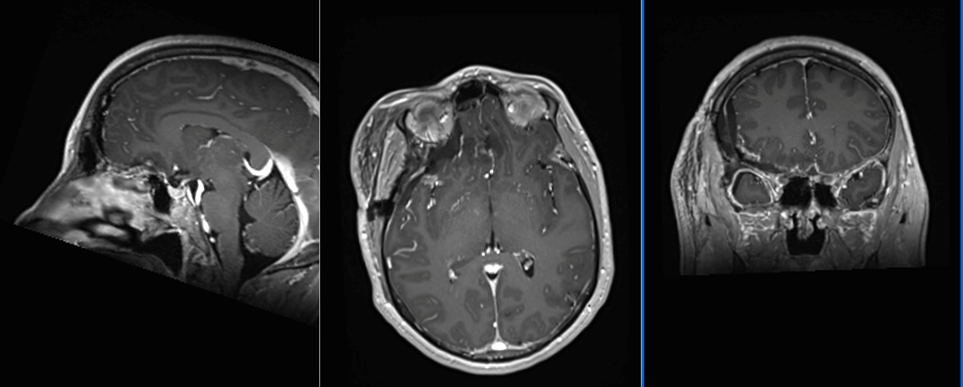

Tumoră de bază de craniu - meningiom olfactiv

Pacientă tânără, în vârstă de 50 ani, diagnosticată în urmă cu 3 ani cu o tumoră de bază de craniu – etaj anterior, cu evoluție progresivă: de la 2 cm diametru în 2019 la 3 cm diametru în februarie 2023.

Tumora era bine delimitată, cu priză omogenă de contrast, și are origine din dura mater (foița externă a meningelui) de la nivelul șanțurilor olfactive – porțiunea din baza craniului pe unde trec nervii olfactivi. Aspectul RMN sugerează un diagnostic histopatologic de meningiom – tumoră benignă (în peste 95% din cazuri) .

Intervenția chirurgicală este cea mai bună soluție în asemenea situații, pentru că, deși benignă, tumora va continua să crească și va începe să determine și alte manifestări neurologice (crize comițiale, afectare vizuală, declin cognitiv – demență, etc.). De asemenea, cu cât tumor este mai mare, cu atât mai lungă și dificilă va fi operația, în timp ce pacientul va fi mai vârstnic și, posibil, cu mai multe suferințe cronice asociate. Un aspect care merită menționat este că portiunea posterioară a tumorii ajunge în apropierea celor doi nervi optici, fără a-i comprima (încă!).

RMN cerebral de control efectuat a doua zi după operație confirmă rezecția completă a tumorii și absența oricăror complicații.